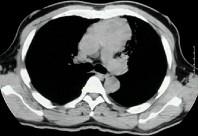

问题 男,26岁,自觉肌无力2周,胸片检查见纵隔增宽,CT检查如,最可能的诊断为 ( )

选项 A.上纵隔畸胎瘤 B.胸内甲状腺瘤 C.中纵隔胸腺瘤侵犯血管 D.淋巴瘤侵犯血管 E.下纵隔畸胎瘤

答案 C